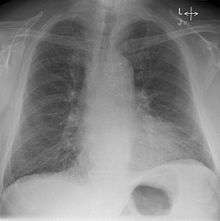

Kerley B lines

These are short parallel lines at the lung periphery. These lines represent interlobular septa, which are usually less than 1 cm in length and parallel to one another at right angles to the pleura. They are located peripherally in contact with the pleura, but are generally absent along fissural surfaces. They may be seen in any zone but are most frequently observed at the lung bases at the costophrenic angles on the PA radiograph, and in the substernal region on lateral radiographs. [2]Causes of Kerley B lines include; pulmonary edema, lymphangitis carcinomatosa and malignant lymphoma, viral and mycoplasmal pneumonia, interstitial pulmonary fibrosis, pneumoconiosis, sarcoidosis. They can be an evanescent sign on the CXR of a patient in and out of heart failure.